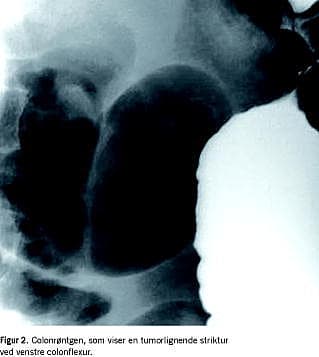

Oversigt over abdomen viste colonileus med flere væskespejl (Figur 1 ). Colonindhældning viste en ca. 2 cm lang tumorlignende striktur med trådtynd kontrastpassage, som svarede til den proksimale colon decsendens (Figur 2 ).

Billedet tolkedes som colonileus pga. colontumor lige analt for flexura coli sinistra. Der blev foretaget koloskopi med henblik på anlæggelse af en colonstent.